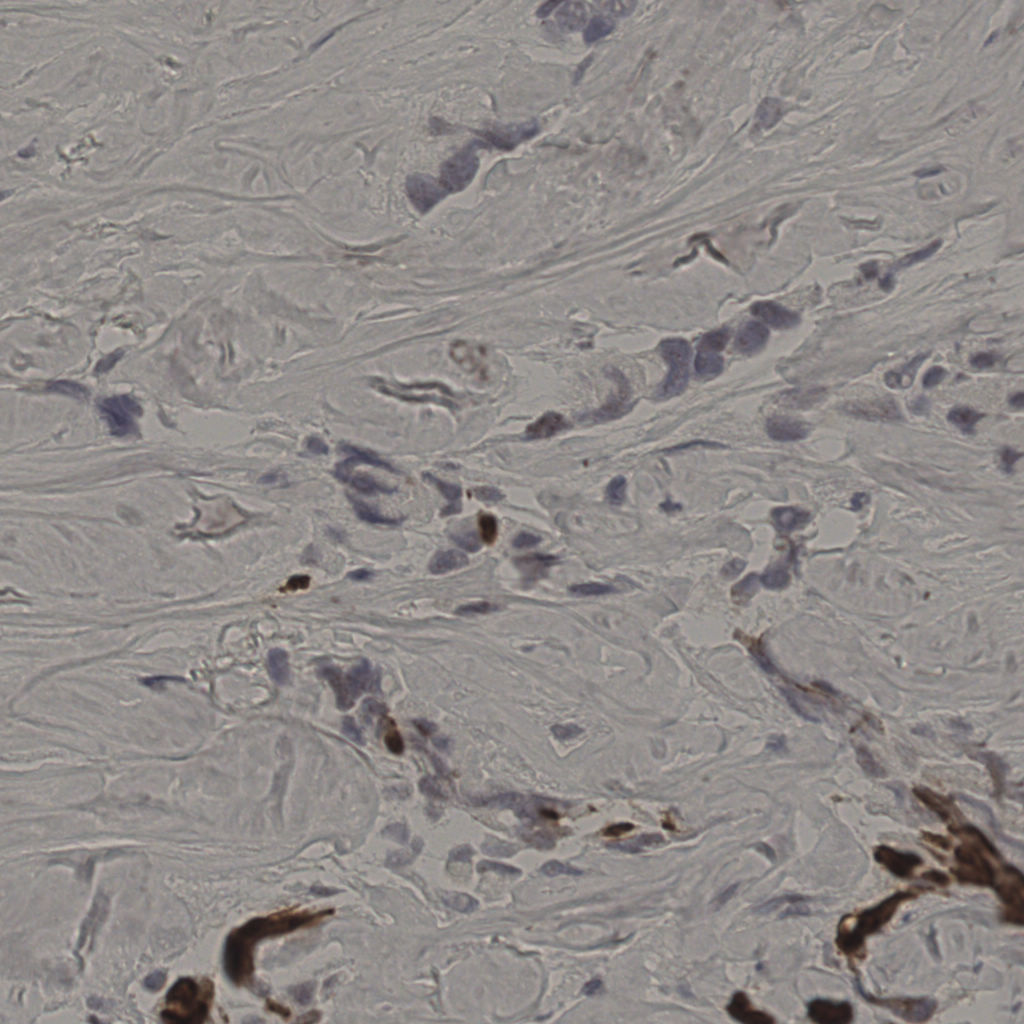

17.75%

Ki67 指数

阴 7986

阳 1723

切片统计

总切片

2640

有效

412

已标记

412

有效率

16%